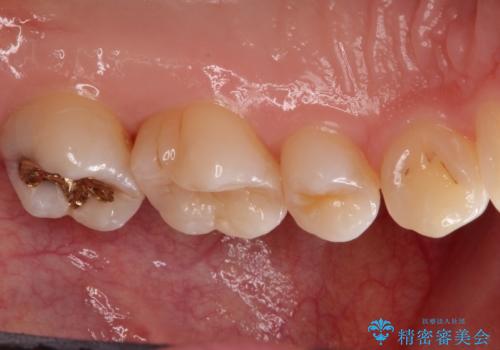

一度治療した歯が虫歯に セラミックインレーで治療

- 他院で虫歯になっていると指摘され来院されました。適合の良いゴールドインレーによる治療がされていましたが、違う部分が虫歯になってしまっていました。審美性の良いセラミックインレーを希望されました。

- 7万円(セラミックインレー)費用は治療当時の料金となります

ゴールドインレーを除去し、その下で広がっていた虫歯をきれいに取り除きました。

一度治療した歯も再び虫歯になる可能性があるので、定期的なチェックが大切になります。